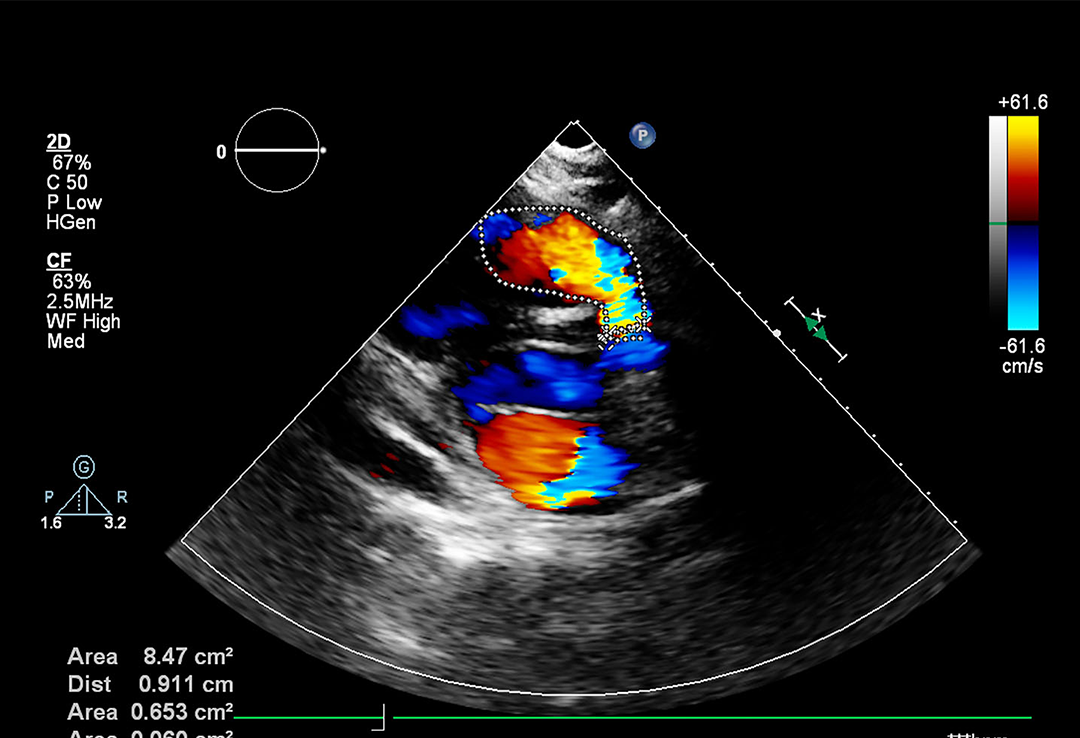

ECHO

This division of ours specializes in providing anesthesia care, pain management, and critical care medicine.